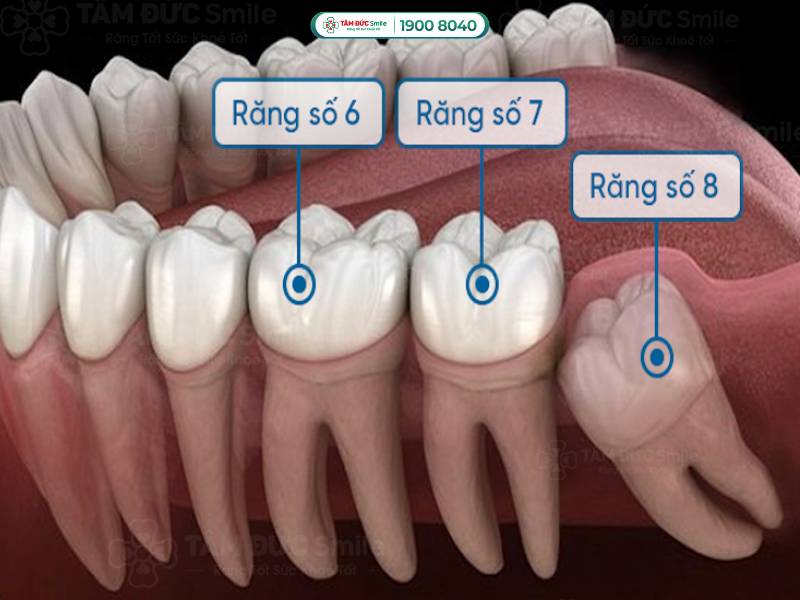

Răng số 7 nằm ở vị trí trong cùng của hàm, mọc trong độ tuổi từ 12-13 khi trẻ đã thay hết răng sữa. Nhiệm vụ quan trọng của răng số 7 là nhai và nghiền thức ăn, tạo thành một hệ thống nhai hoàn chỉnh. Vì kích thước lớn nên cấu tạo của chiếc răng này rất phức tạp, có 2-3 chân răng và nhiều rãnh trên bề mặt.

Tuy nhiên, vì nằm ở vị trí khuất và có cấu tạo phức tạp, răng số 7 dễ mắc các bệnh lý về răng miệng. Mọi người khó vệ sinh chiếc răng ở tận trong cùng, nếu xuất hiện lỗ sâu cũng dễ bị bỏ qua. Ngoài ra, vùng kẽ răng giữa số 7 và số 8 (răng khôn) lớn trở thành nơi lý tưởng của mảng bám, cao răng, vi khuẩn, dị vật,...

Răng số 7 và số 8 nằm ở vị trí trong cùng của hàm